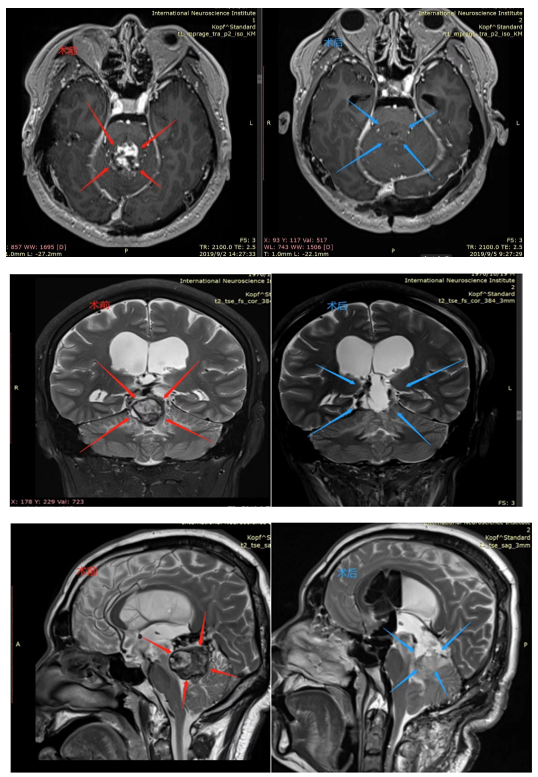

术前(红色):在松果体区域显示出对比度增强的团块,并向下延伸到四脑室。脑干出现水肿。

术后(蓝色):松果体肿瘤被完整切除,无严重神经功能损伤(有填充物)